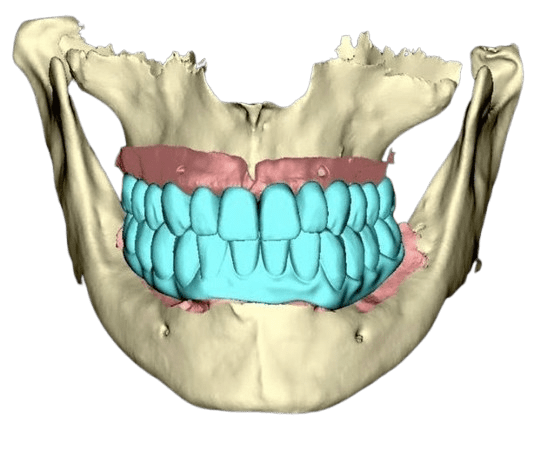

Bei fortgeschrittenem horizontalem Knochenabbau öffnen sich die Zahnzwischenräume, was eine erhebliche ästhetische und funktionelle Herausforderung darstellt. In solchen Fällen sind die parodontologischen Behandlungsmöglichkeiten begrenzt: Eine vollständige Knochenregeneration ist oft nicht möglich. Prothetische Lösungen – wie beispielsweise die Anfertigung einer reinigungsfähigen und waschbaren Brücke – gewährleisten in diesen Fällen eine optimale Mundhygiene und langfristige Stabilität des betroffenen Bereichs und streben ein bestmögliches ästhetisches Ergebnis an.

Ist eine zahnärztliche Versorgung nach FP1-Standard nicht möglich und kann horizontaler oder vertikaler Knochenverlust nicht ausgeglichen werden, kommen alternative Methoden zum Einsatz. Bei mäßigem Knochenverlust und massivem Weichgewebsverlust – oder wenn der Patient aus Zeitgründen, finanziellen Erwägungen oder aufgrund von Angst keine Knochen- und Weichgewebsaugmentation wünscht – stellt die Versorgung nach FP2-Standard die ideale Lösung dar. Hierbei wird rosafarbene Keramik verwendet, die das fehlende Weichgewebe ästhetisch ersetzt und gleichzeitig ein stabiles und dauerhaftes Ergebnis gewährleistet.

Bei einem größeren Knochen- und Weichteildefekt ersetzen wir im Rahmen des festsitzenden Zahnersatzes 3 sowohl den Knochen als auch das Zahnfleisch durch die Zahnprothese (entweder Zirkon- oder Kunststoffprothesen - mit individuell ausgewählten Zähnen aus einem hochwertigen Premium-Set und einer Zahnfleischimitation, zum Beispiel aus Gradia-Material).